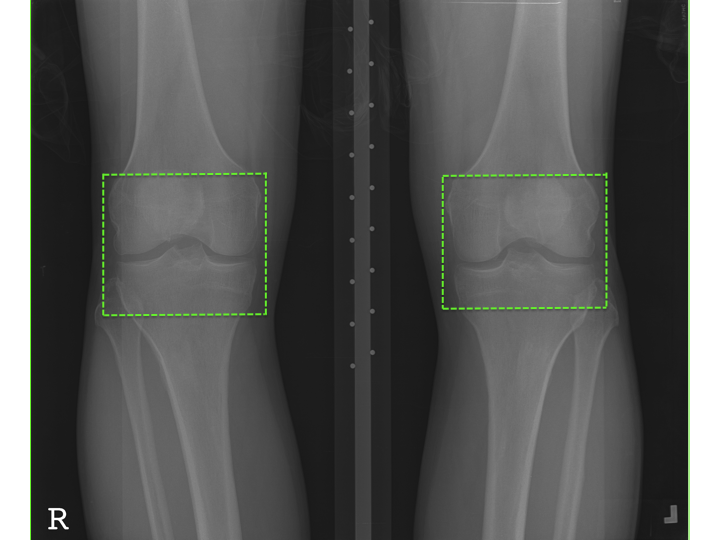

4.1 Automatically Localizing Knee Joints using a FCN

Assessment of knee OA severity can be achieved by detecting the variations in joint space width and osteophytes formation in the knee joint [10]. Thus, localizing the knee joints from the X-ray images is an essential pre-processing step before quantifying knee OA severity, and for larger datasets automatic methods are preferable. Figure 3 shows a knee OA radiograph and the knee joints: the region of interest (ROI) for detection. The previous methods for automatically localizing knee joints such as template matching [14] and our own SVM-based method [1] are not very accurate. In this study, we propose a fully convolutional neural network (FCN) based approach to further improve the accuracy and precision of detecting knee joints.

Refer to caption

Figure 3: A knee OA X-ray image with the region of interest: the knee joints.